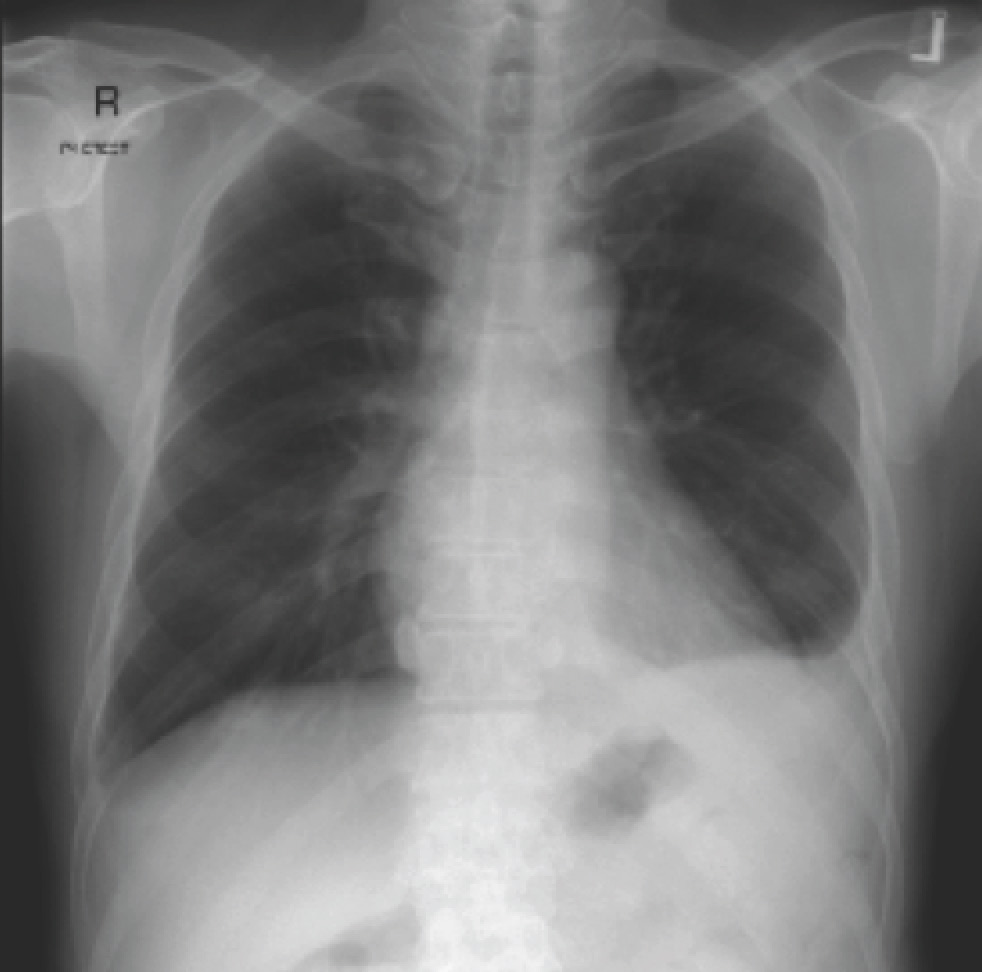

A middle-aged (60-year-old) man with Type 2 diabetes mellitus and past history of tuberculosis presented with low-grade fever for 2 weeks and a 1.5 cm nodule over his left lower back (approximately L1 level). This was determined to be an abscess and creamy white pus was aspirated by his general practitioner. The Gram stain showed Gram-negative bacilli, and his chest X-ray (and a segment of the subsequent CT abdomen) is shown below.

The CT abdomen shows an irregular spleen with multiple hypodense lesions. In this context, it represents splenic abscesses. The chest X-ray shows blunting of the left costophrenic angle, representing a pleural effusion. The lower back nodule represents an abscess – in this case linked by a sinus tract to the spleen. Taking everything into consideration – Gram-negative bacteria, patient with diabetes mellitus, splenic abscesses, tropical country – the Gram-negative bacteria is almost invariably going to be Burkholderia pseudomallei, the causative agent of melioidosis. There are two key review papers – the first published in 2005 in Clinical Microbiology Reviews, and the second (behind a pay wall) published in 2012 in the New England Journal of Medicine. Current treatment protocols involve prescription of intravenous ceftazidime for 2 weeks followed by a prolonged course of oral trimethoprim/sulfamethoxazole +/- doxycycline.